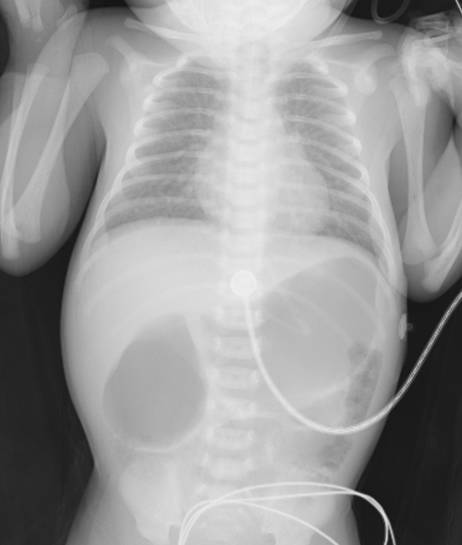

患儿经过补液纠正电解质紊乱后,无再发抽搐,精神好转,临床症状改善,病情较入院稳定,X片检查:

患儿除了肺部少许渗出,提示肺炎,腹部有典型的双泡征,考虑十二指肠远端狭窄可能性大,后来完善消化道造影检查,证实为十二指肠远端狭窄,送小儿外科继续外科治疗。